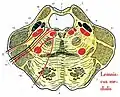

В последние годы жизни в Галле Рейль заинтересовался нейроанатомией, особенно после лекции, которую летом 1805 прочитал френолог Ф. И. Галль. Иоганн Христиан Рейль начал изучать мозжечок, публикуя большинство работ в 1807-1809. Он известен в анатомии мозга множественными эпонимами после изучения его строения и химического состава:

- Дугообразный пучок (пучок Рейля, лат. fasciculus arcuatus) соединяет клетки язычка, клетки ядра шатра с латеральным, медиальным и верхним преддверными ядрами;

- Рейля циркулярная борозда (синоним: круговая борозда островка, лат. sulcus circularis insulae);[15]

- Рейля углубление (синоним: долинка мозжечка, лат. vallecula cerebelli);

- Рейля треугольник (синоним: треугольник петли, лат. trigonum lemnisci);

- Рейля связка (синоним: медиальная петля, лат. lemniscus medialis);

- Рейля петля (синоним: петля мозговой ножки, лат. ansa peduncularis);

- Рейля островок (синоним: островковая доля, лат. lobus insularis);

- Рейля волокна (синоним: латеральные полоски мозолистого тела, лат. striae longitudinales laterales);

- Он первым описал структуру, известную как покрышка (лат. tapetum) мозолистого тела;

Рейля островок (здесь и далее структура отмечена красным)

Рейля островок (здесь и далее структура отмечена красным) Рейля петля

Рейля петля Треугольник Рейля

Треугольник Рейля Углубление Рейля

Углубление Рейля